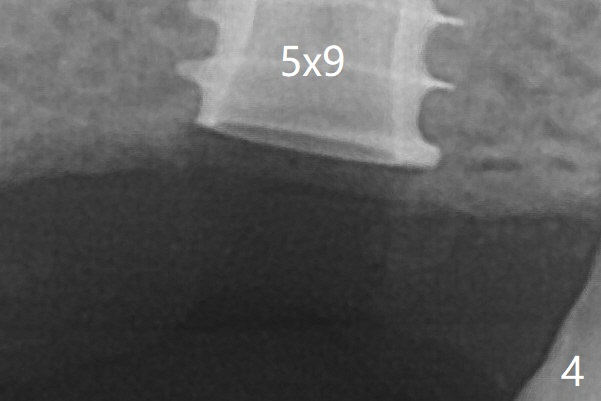

A BW shows that the implant is placed slightly subcrestal (Fig.4). The bone resorption seems to be worse 8 months post cementation (Fig.8,9, compare Fig.7); in fact the abutment screw is loose. The gingiva is healthy.